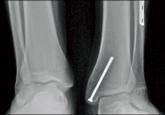

The fibula is an important stabilizer of the lateral ankle. Discontinuity of the fibular shaft can lead to progressive pain and shortening of the...